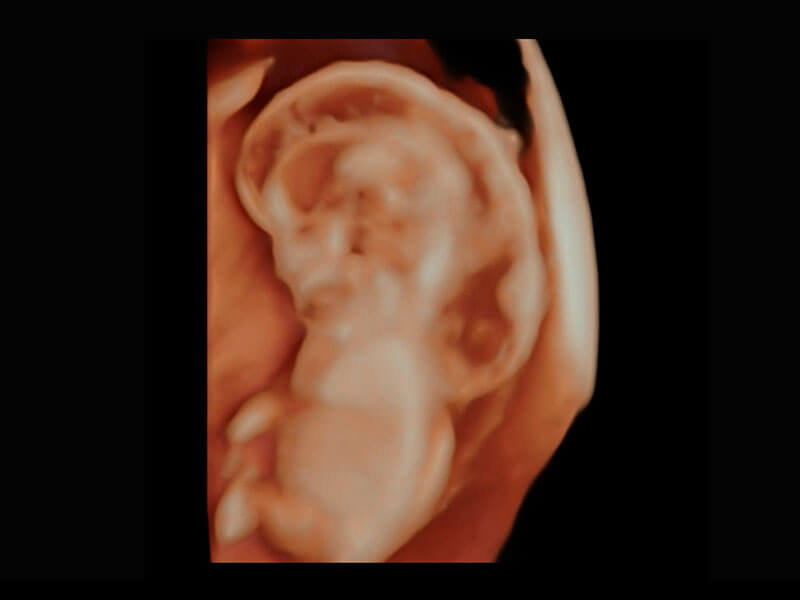

早孕筛查

根据国际妇产科超声协会ISUOG统计,早孕超声筛查结合胎儿游离染色体筛查(NIPT),能够检出大部分胎儿染色体异常疾病,P60在胎儿早孕期超声筛查中为您带来优异的图像质量。

• 早孕-胎心

• 高分辨率容积成像-早孕胎儿

• 胎儿体循环

• 光影成像-孕囊